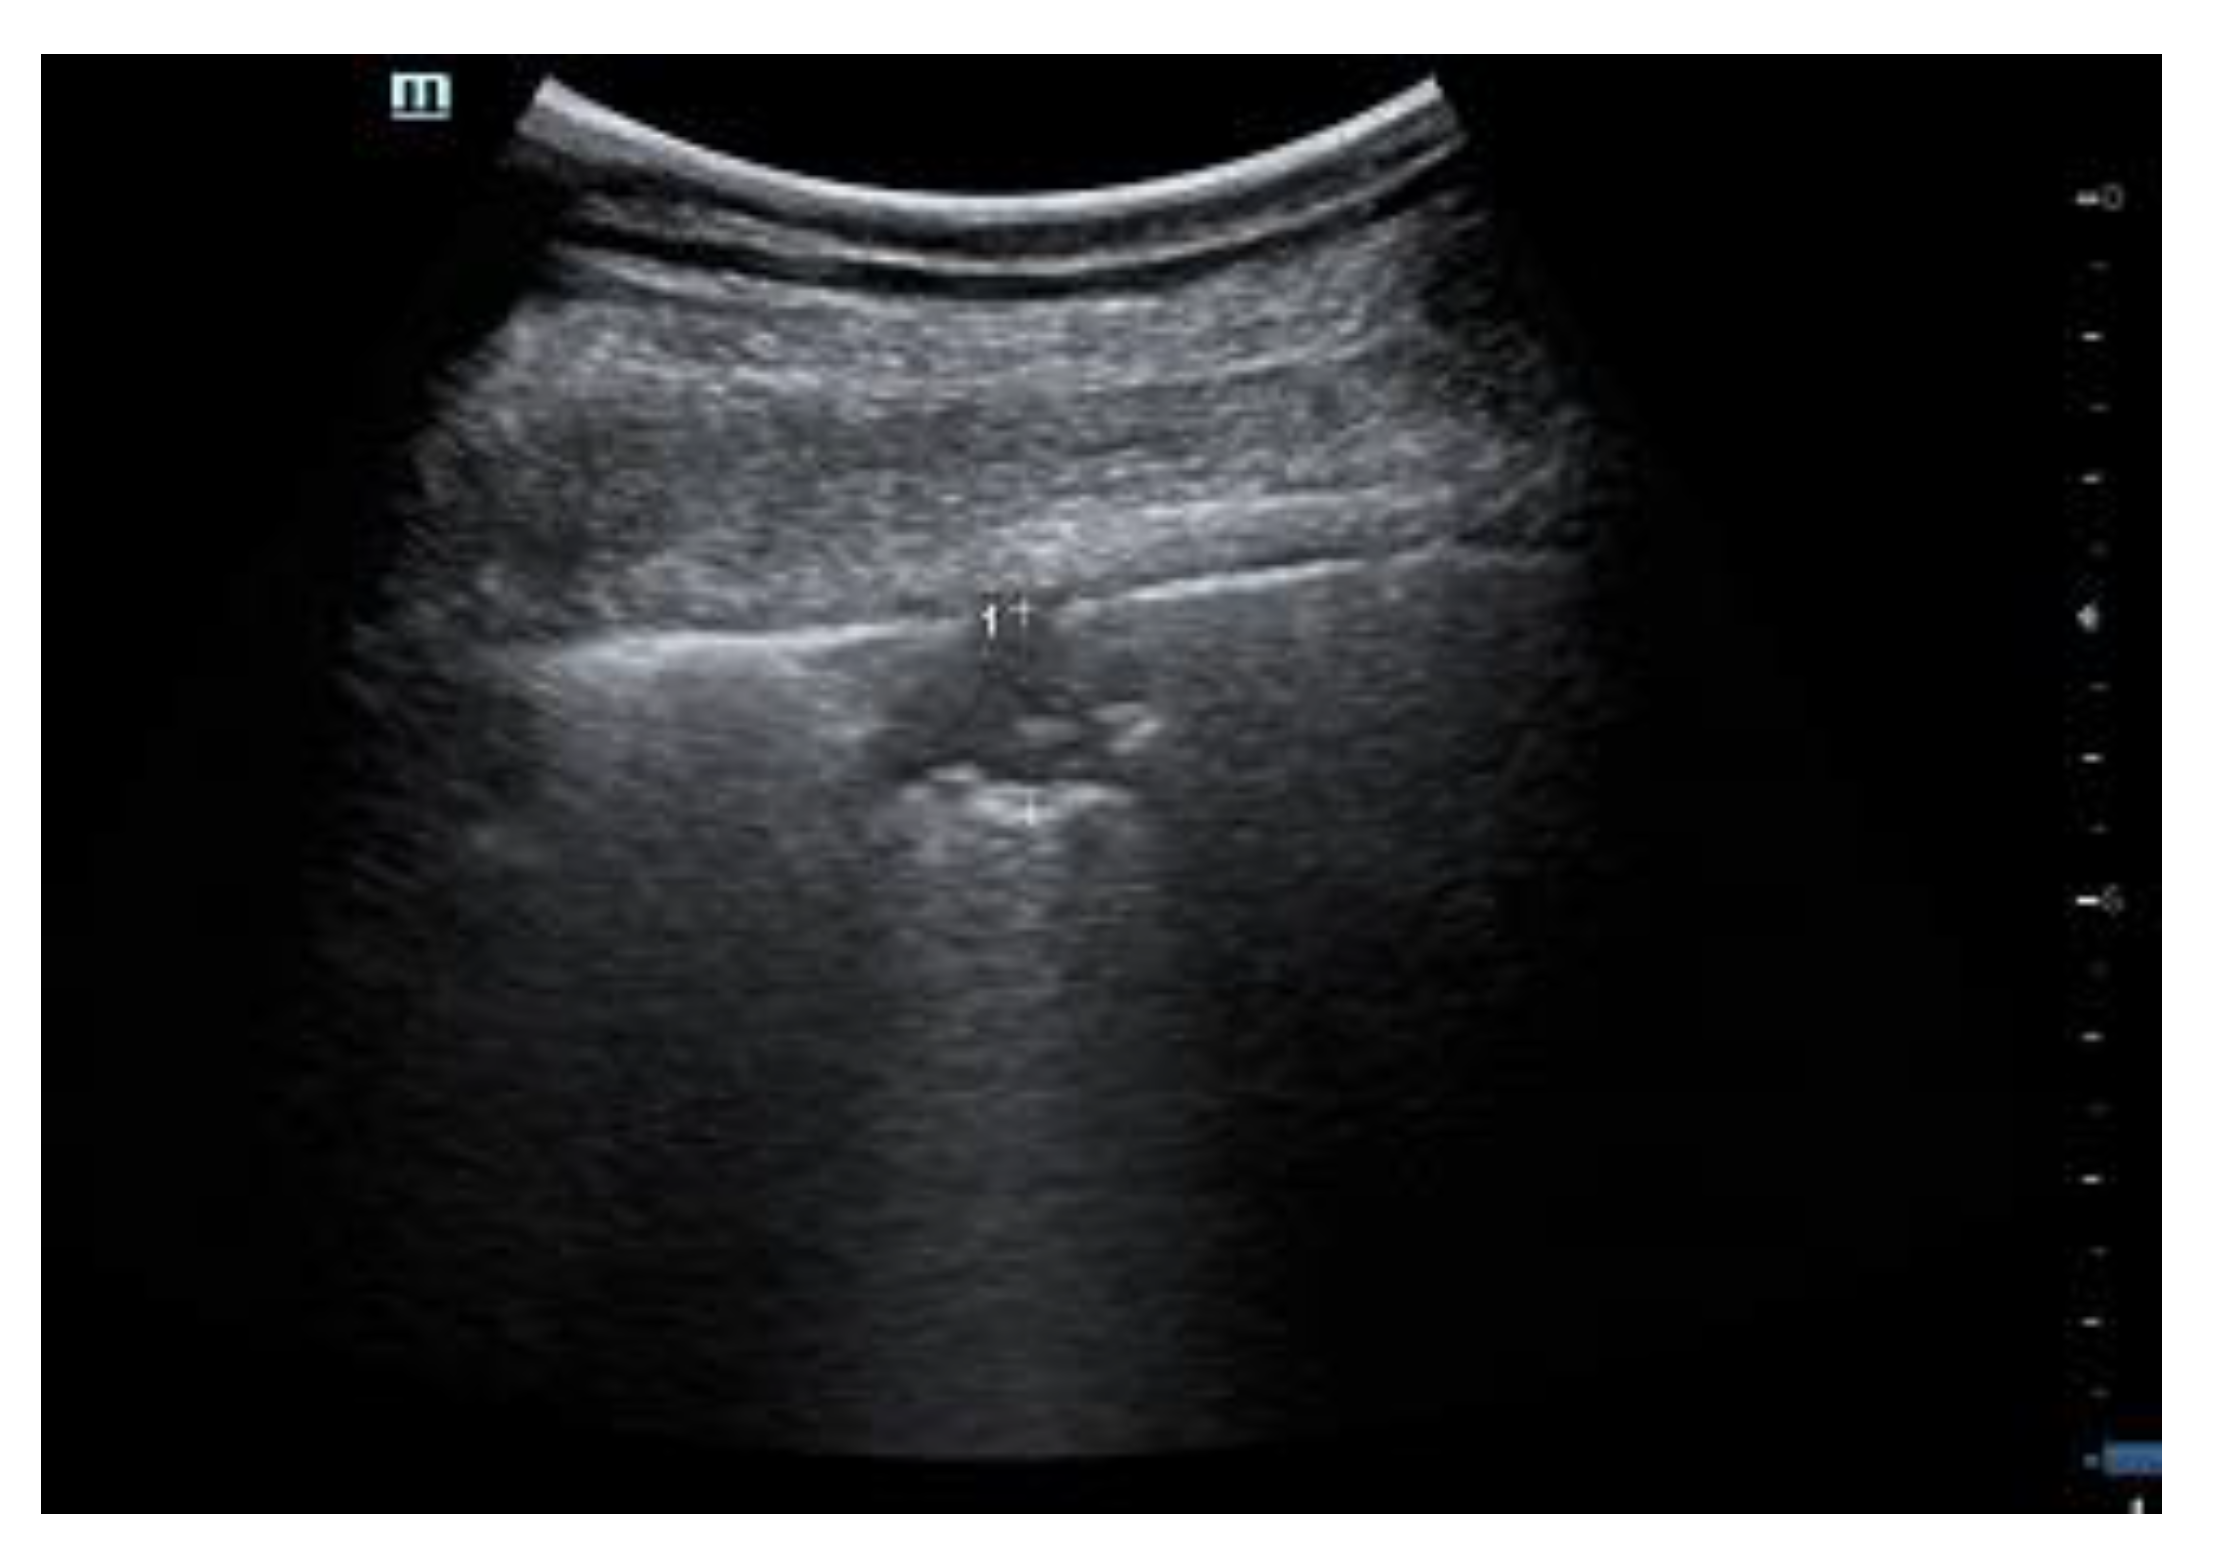

2.1. Characteristics of the Pleural Line

| 2 | Pleural line has relevant alterations. Progression of subversion of peripheral air space geometry causes a predominance of vertical artifacts. Small subpleural consolidations, related to deaeration, can be present. |

| 3 | Pleural line is irregular and cobbled. Subpleural lung is denser and more disordered. White lung with or without larger consolidations may be present. Small and large consolidations are subpleural regions minimally or completely deprived of air. |